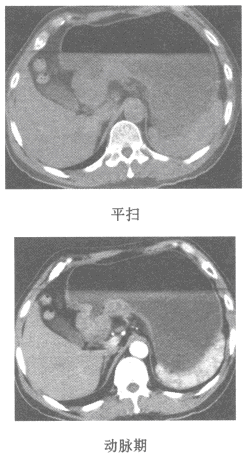

女,45岁,抑郁嗜睡1月,实验室检查血钙3mml/L,CT图像如图,最可能的诊断为()

A.正常

B.永存上腔静脉干

C.胸内甲状旁腺瘤

D.胸内甲状腺瘤

E.囊性胸腺瘤